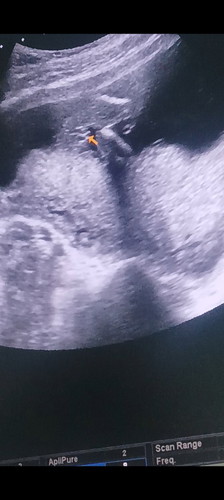

แม่ๆว่าเพศอะไรค่ะ

บ้านนี้ไม่แน่ใจเลย หมอบอกว่าผู้หญิงแต่ลูกหนีบขาเลยไม่แน่ใจ